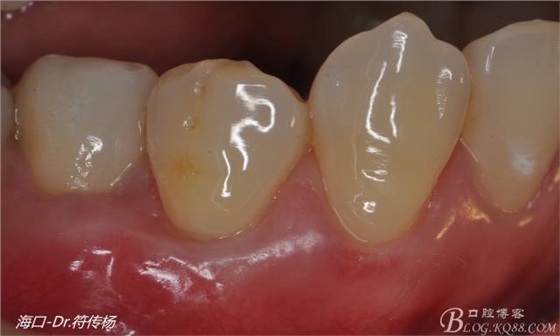

今天給大家分享一例較為標(biāo)準(zhǔn)的根面覆蓋手術(shù)病例

從病例圖片我們可以看到44牙頰側(cè)牙齦出現(xiàn)明顯萎縮

術(shù)前評(píng)估:退縮的齦緣在MGJ冠方 近遠(yuǎn)中牙槽嵴頂高度正常屬于Miller -Ι類牙齦退縮 所有術(shù)后可以完全覆蓋